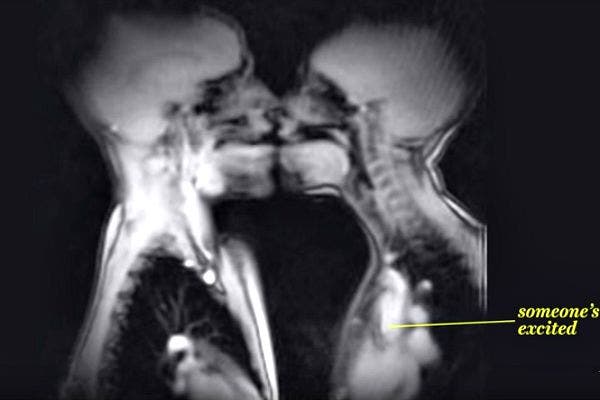

2. Let the French kissing commence.

Ida Sabelis, a Dutch anthropologist and one of the subjects of the study said, "On a certain moment there's sounding through the microphone. The erection is fully visible, including the root."

3. No, your eyes aren't deceiving you.

Yep, put that on your list of "things I never thought I'd see, and probably never want to see again."